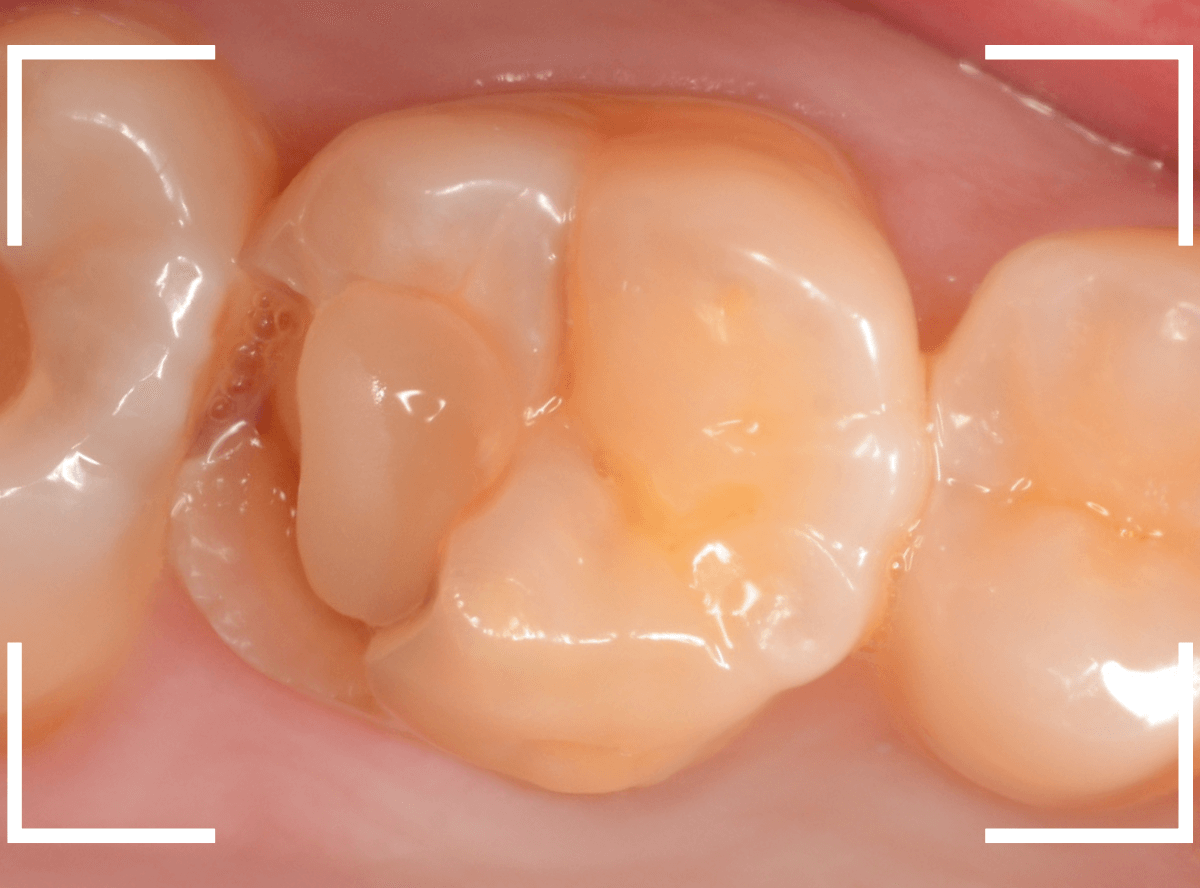

奥歯で咬んだ時に、痛みを感じるという訴えで来院された患者さんです。

パッと見は特に問題なさそうな状態ですが、大きなレジン治療がしてあり、レジンの奥もボヤっと黒っぽく見えてアヤシイ感じです。

レントゲン写真で確認します。

青い線が神経、赤い線が虫歯です。

神経に触ってしまいそうなほどの大きな虫歯です。

(隣の歯も虫歯がありそうです)

麻酔をして、レジンを外します。

レントゲン写真から想定できるような大きな虫歯ですね。

慎重に虫歯を除去します。

赤く染色されている部分が虫歯の残っている部分です。

全ての虫歯を除去したところです。

何とか神経の寸前で虫歯を食い止める事ができましたが、まれに症状が出る事もありますのでお薬をつめてしばらく経過観察します。